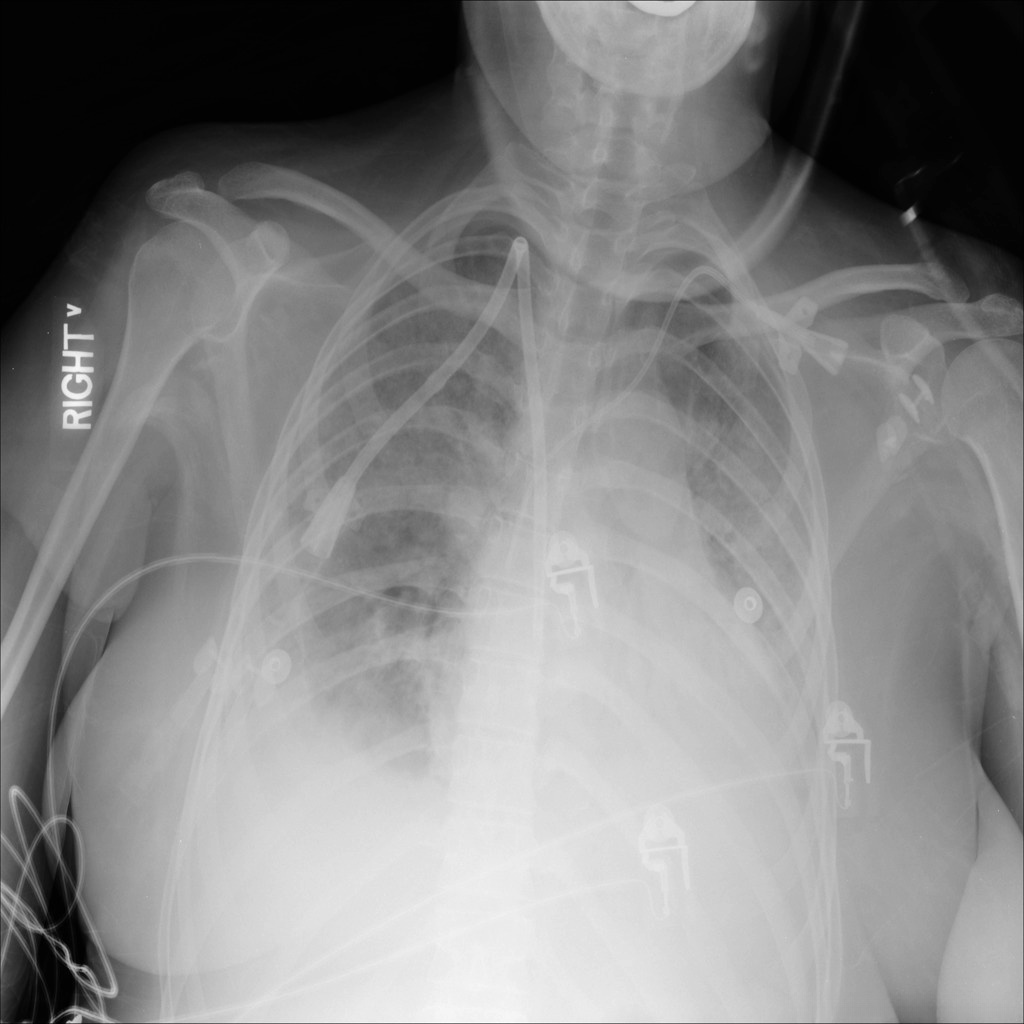

由放射学会国家联盟于2018年发起的RSNA Pneumonia Detection Challenge旨在推动自动化肺炎检测技术的进步与应用。该挑战提供了一个包含约30,000份患者胸部X光片的数据集,并对其中每张图片都进行了标注以确定是否存在肺结核情况。这些来自不同医疗中心的影像资料涵盖了多种X光成像系统与设备的应用场景

在完成处理后,并对图像进行肺炎标注的目标检测数据集中共有6012张图像被分类为病变区域。